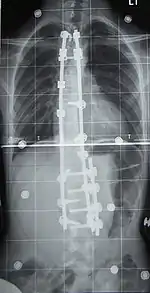

Surgery is usually recommended by orthopedists for curves with a high likelihood of progression (i.e., greater than 45–50° of magnitude), curves that would be cosmetically unacceptable as an adult, curves in people with spina bifida and cerebral palsy that interfere with sitting and care, and curves that affect physiological functions such as breathing.[103][104]

Surgery is indicated by the Society on Scoliosis Orthopaedic and Rehabilitation Treatment (SOSORT) at 45–50°[4] and by the Scoliosis Research Society (SRS) at a Cobb angle of 45°.[105] SOSORT uses the 45–50° threshold as a result of the well-documented, plus or minus 5° measurement error that can occur while measuring Cobb angles.[105]

Surgeons who are specialized in spine surgery perform surgery for scoliosis. To completely straighten a scoliotic spine is usually impossible, but for the most part, significant corrections are achieved.[106]

The two main types of surgery are:

- Anterior fusion: This surgical approach is through an incision at the side of the chest wall.

- Posterior fusion: This surgical approach is through an incision on the back and involves the use of metal instrumentation to correct the curve.

One or both of these surgical procedures may be needed. The surgery may be done in one or two stages and, on average, takes four to eight hours.

In 1962, the American orthopaedic surgeon Paul Harrington introduced a metal spinal system of instrumentation that assisted with straightening the spine, as well as holding it rigid while fusion took place. The now obsolete Harrington rod operated on a ratchet system, attached by hooks to the spine at the top and bottom of the curvature that when cranked would distract—or straighten—the curve. The Harrington rod obviates the need for prolonged casting, allowing patients greater mobility in the postoperative period and significantly reducing the quality of life burden of fusion surgery. The Harrington rod was the precursor to most modern spinal instrumentation systems. A major shortcoming was that it failed to produce a posture wherein the skull would be in proper alignment with the pelvis, and it did not address rotational deformity. As the person aged, there would be increased wear and tear, early onset arthritis, disc degeneration, muscular stiffness, and acute pain. "Flatback" became the medical name for a related complication, especially for those who had lumbar scoliosis.[116]

In the 1980s, Cotrel–Dubousset instrumentation improved fixation and addressed sagittal imbalance and rotational defects unresolved by the Harrington rod system. This technique used multiple hooks with rods to give stronger fixation in three dimensions, usually eliminating the need for postoperative bracing.[117]